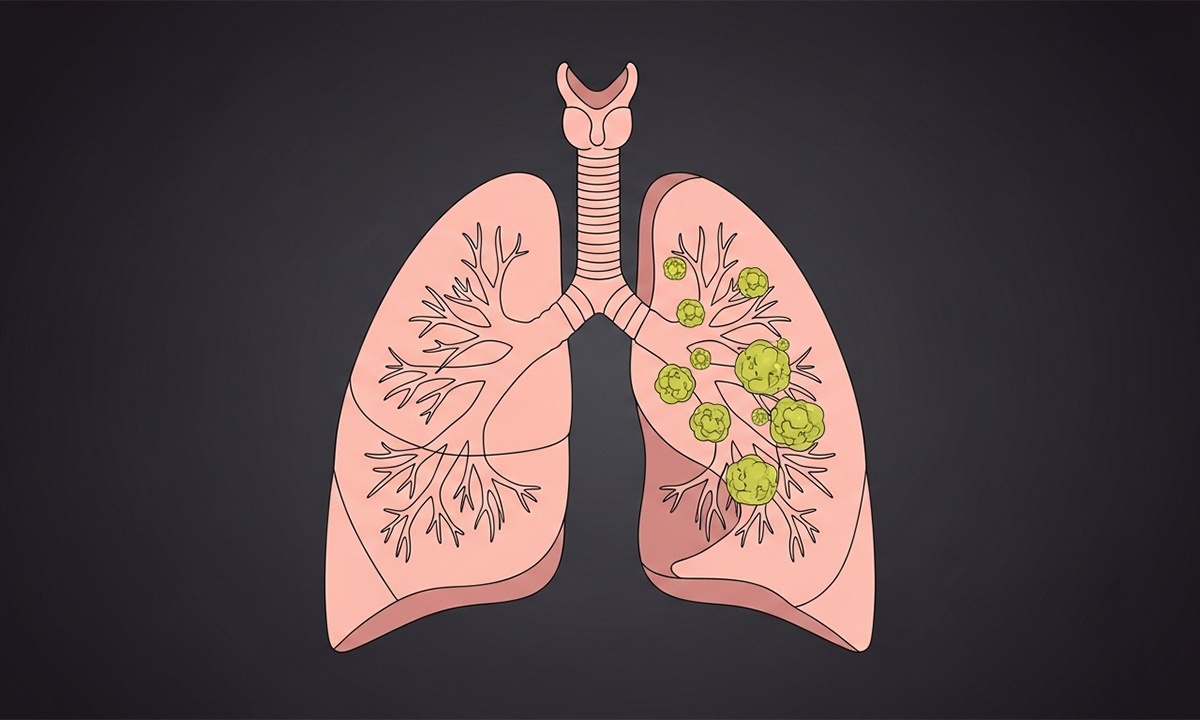

يعد النمو الخلوي غير المنضبط في أنسجة الجهاز التنفسي من أخطر التحديات الصحية المعاصرة التي تتطلب تشخيصاً دقيقاً للغاية، وتؤدي الإصابة بمرض سرطان الرئة إلى تدمير الحويصلات الهوائية المسؤولة عن تبادل الأكسجين والغازات الحيوية الضرورية لاستقرار الأنظمة الفسيولوجية،

وتعتمد فعالية العلاج بشكل أساسي على الاكتشاف المبكر للعلامات السريرية وفهم العوامل البيئية والجينية التي تحفز التحولات الخلوية الضارة بداخل الرئتين لضمان استدامة الصحة العامة للمرضى.